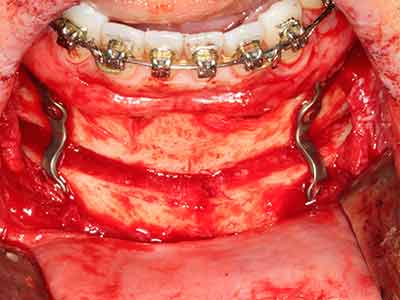

Indikation: Bone Splitting

Knochengewebe ist nicht nur rein mineralisch, sondern auch in wesentlichen Anteilen aus Kollagenfasern aufgebaut. Dies gewährleistet neben einer guten Druckfestigkeit eine gewisse Flexibilität, welche für die Durchführung von Augmentationen genutzt werden kann. Bei der klassischen Expansionsplastik im Sinne eines Bone Splittings wird der atrophierte Kieferkamm in seiner Längsachse gespalten und nach Erreichen einer ausreichenden Osteotomietiefe vorsichtig aufgedehnt (Abb. 13-16), idealerweise ohne den Kiefer wesentlich zu deperiostieren (Brugnami, Caiazzo et al. 2014, Stricker, Fleiner et al. 2014). Bewährt haben sich Schrauben- und Plattensysteme mit zunehmender Expansionsdistanz, um die beiden Knochenlamellen unterhalb der Bruchschwelle voneinander zu distanzieren. In der Regel werden Restknochenbreiten von mindestens 3-4 mm gefordert (Chiapasco, Zaniboni et al. 2006), um eine ausreichende Flexibilität und knöcherne Bedeckung der einzubringenden Implantate zu gewährleisten. Ggf. kann eine ein- oder beidseitige vertikale Entlastungsosteotomie die Flexibilität verbessern. Als Alternative zur klassischen Technik wurde eine Kombination mit weiteren augmentativen Techniken vor allem auf der bukkalen Seite beschrieben.

Mittels Piezosägen erfolgt die Anlage des Splittings besonders schonend und ohne wesentliche Dimensionsverluste, so dass sich keine signifikanten Unterschiede von Implantaten im gesplitteten Kiefer im Vergleich zum nicht defizitären Alveolarkamm gezeigt haben (Chiapasco, Zaniboni et al. 2006, Danza, Guidi et al. 2009). Gerade beim lokal begrenzten und tiefen Splitting ist jedoch stets auf eine ausreichende Wasserkühlung zu achten, um thermische Belastungen in den apikalen Osteotomiebereichen zu vermeiden.